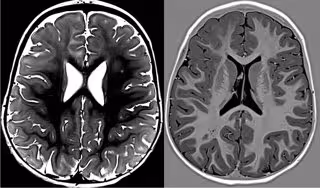

Imagen de la identificación del nuevo tipo de epilepsia.

Imagen de la identificación del nuevo tipo de epilepsia. - QUIRÓNSALUD